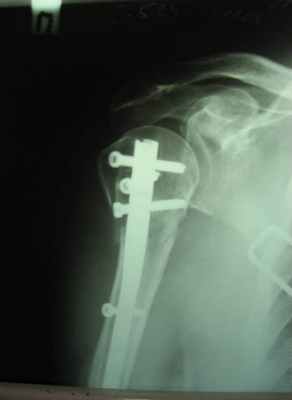

Пациентка с тяжелым переломом верхнего отдела (хирургической шейки) плечевой кости.

Рентгенограмма до операции.

Выполнена операция: металлоостеосинтез плечевой кости современной полиаксиальной пластиной LCP.

Гипсовая повязка после операции не применялась, сразу разрешен полный объем движений в плечевом суставе, разработка суставов. Пациентка смогла выйти на работу через несколько дней после операции, полностью обслуживала себя в быту, носила нормальную одежду, т.е. в ближайшие сроки после операции вернулась к нормальной жизни.

Результат через 1 мес. после операции. Функция конечности полностью восстановлена.